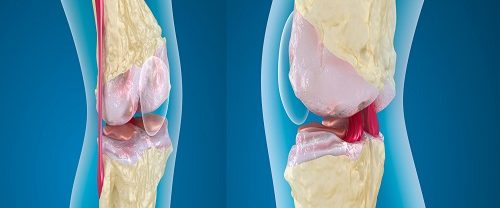

Osteoartrit Nedir? Osteoartrit, eklemlerdeki kıkırdak dokusunun zamanla aşınması ve bozulması sonucu gelişen bir eklem hastalığıdır. Bu durum, eklemlerin rahat hareket etmesini sağlayan kıkırdak dokusunun kaybına ve eklem kenarlarında kemik büyümesine yol açar. Osteoartrit, genellikle yaşlanma süreciyle ilişkilendirilse de, bazı risk faktörleri bu hastalığın ortaya çıkmasına katkıda bulunabilir. Osteoartrit Tanımı ve Nedenleri Osteoartrit, eklemlerdeki kıkırdak dokusunun…

Total Diz Protezi Nedir? Total diz protezi, diz eklemi hasar görmüş veya aşınmış olan yöntemle uygulanan bir cerrahi işlemdir. Bu işlem, diz eklemlerinden bir veya daha fazla bileşenin çıkarılarak yerine suni implantların saklanmasını içerir. Temel amacı, değişimlerin ağrılarını azaltmak, hareket kabiliyetini geri kazanımı ve yaşam sınırlarını arttırmaktır. Total diz protezi, genellikle osteoartrit gibi dejeneratif ekleme…